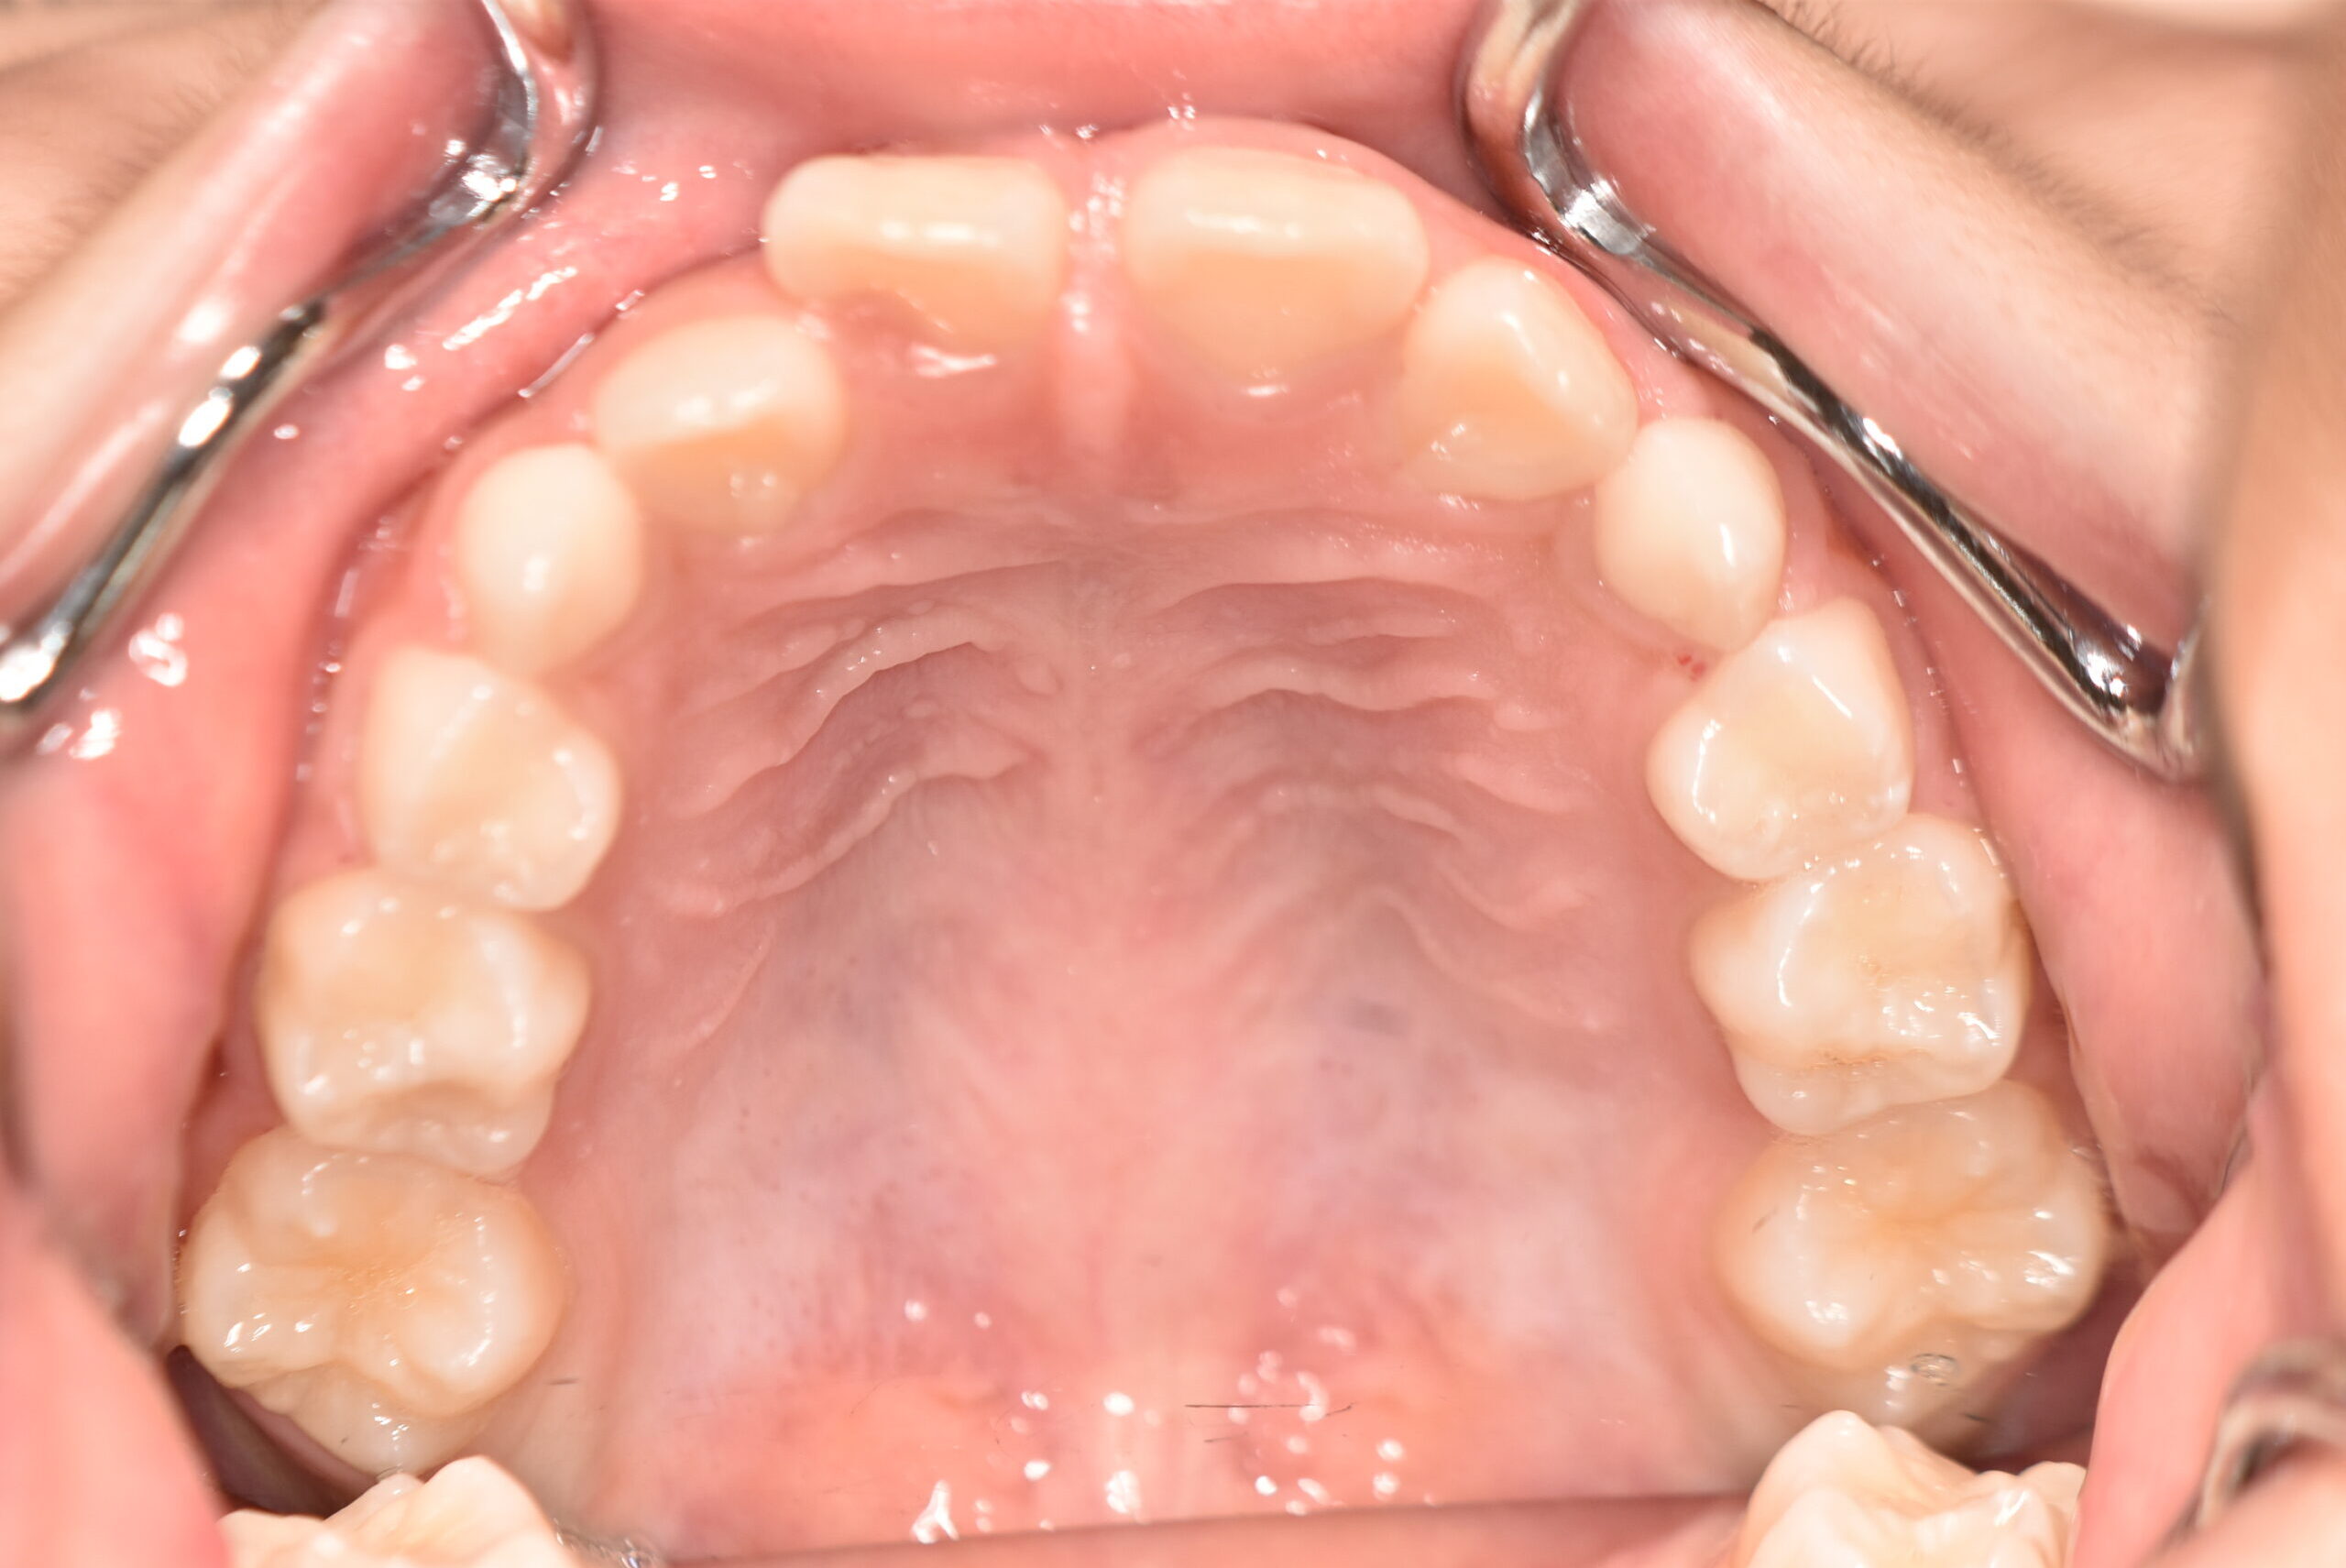

初診時

症例 症例 症例 症例

動的治療終了時

年齢

9歳 性 別 女性

治療期間 7ヶ月 費 用 矯正施術料:750,000円

調整料:4,000円/月

治療内容の詳細 初診時9歳の女児で、歯のがたつきを気にされ来院されました。

検査の結果、前歯部叢生を伴うアングルⅠ級不正咬合と診断しました。

治療としてはマウスピース矯正(インビザラインファースト)で配列を行い、上下顎の側方拡大と萌出スペースを確保しました。

治療期間は、7ヶ月でした。

今後、側方歯生え変わりまで経過観察を行います。